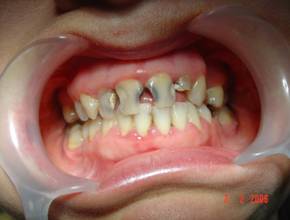

Cazul 2: L.A., fem:

Initial clinic si radiologic se observa prezenta resturilor radiculare frontale superioare.

Cazul dupa restaurarea functiei fizionomice.